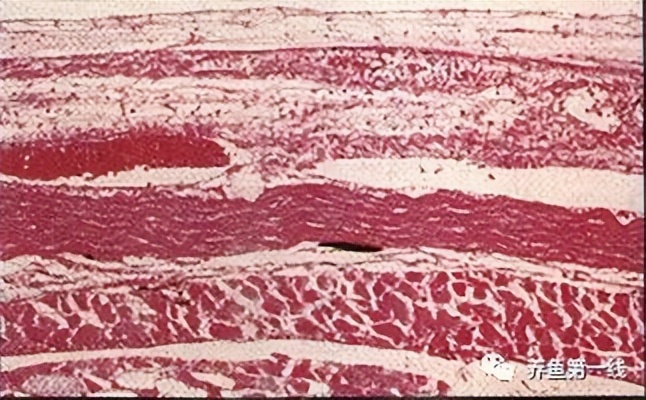

[病因]

病原菌为无色分枝杆菌(Mycobacterium nonchromogenicum),是一种 抗酸菌 。本菌被石炭酸品红染色不呈红色。在组织内形成特征的 结节状肉芽肿 。在病原菌的培养方面,将病灶用4%苛性钠处理后,用3%小田培养培养约4周后,可长出灰白色菌落(照片3)。